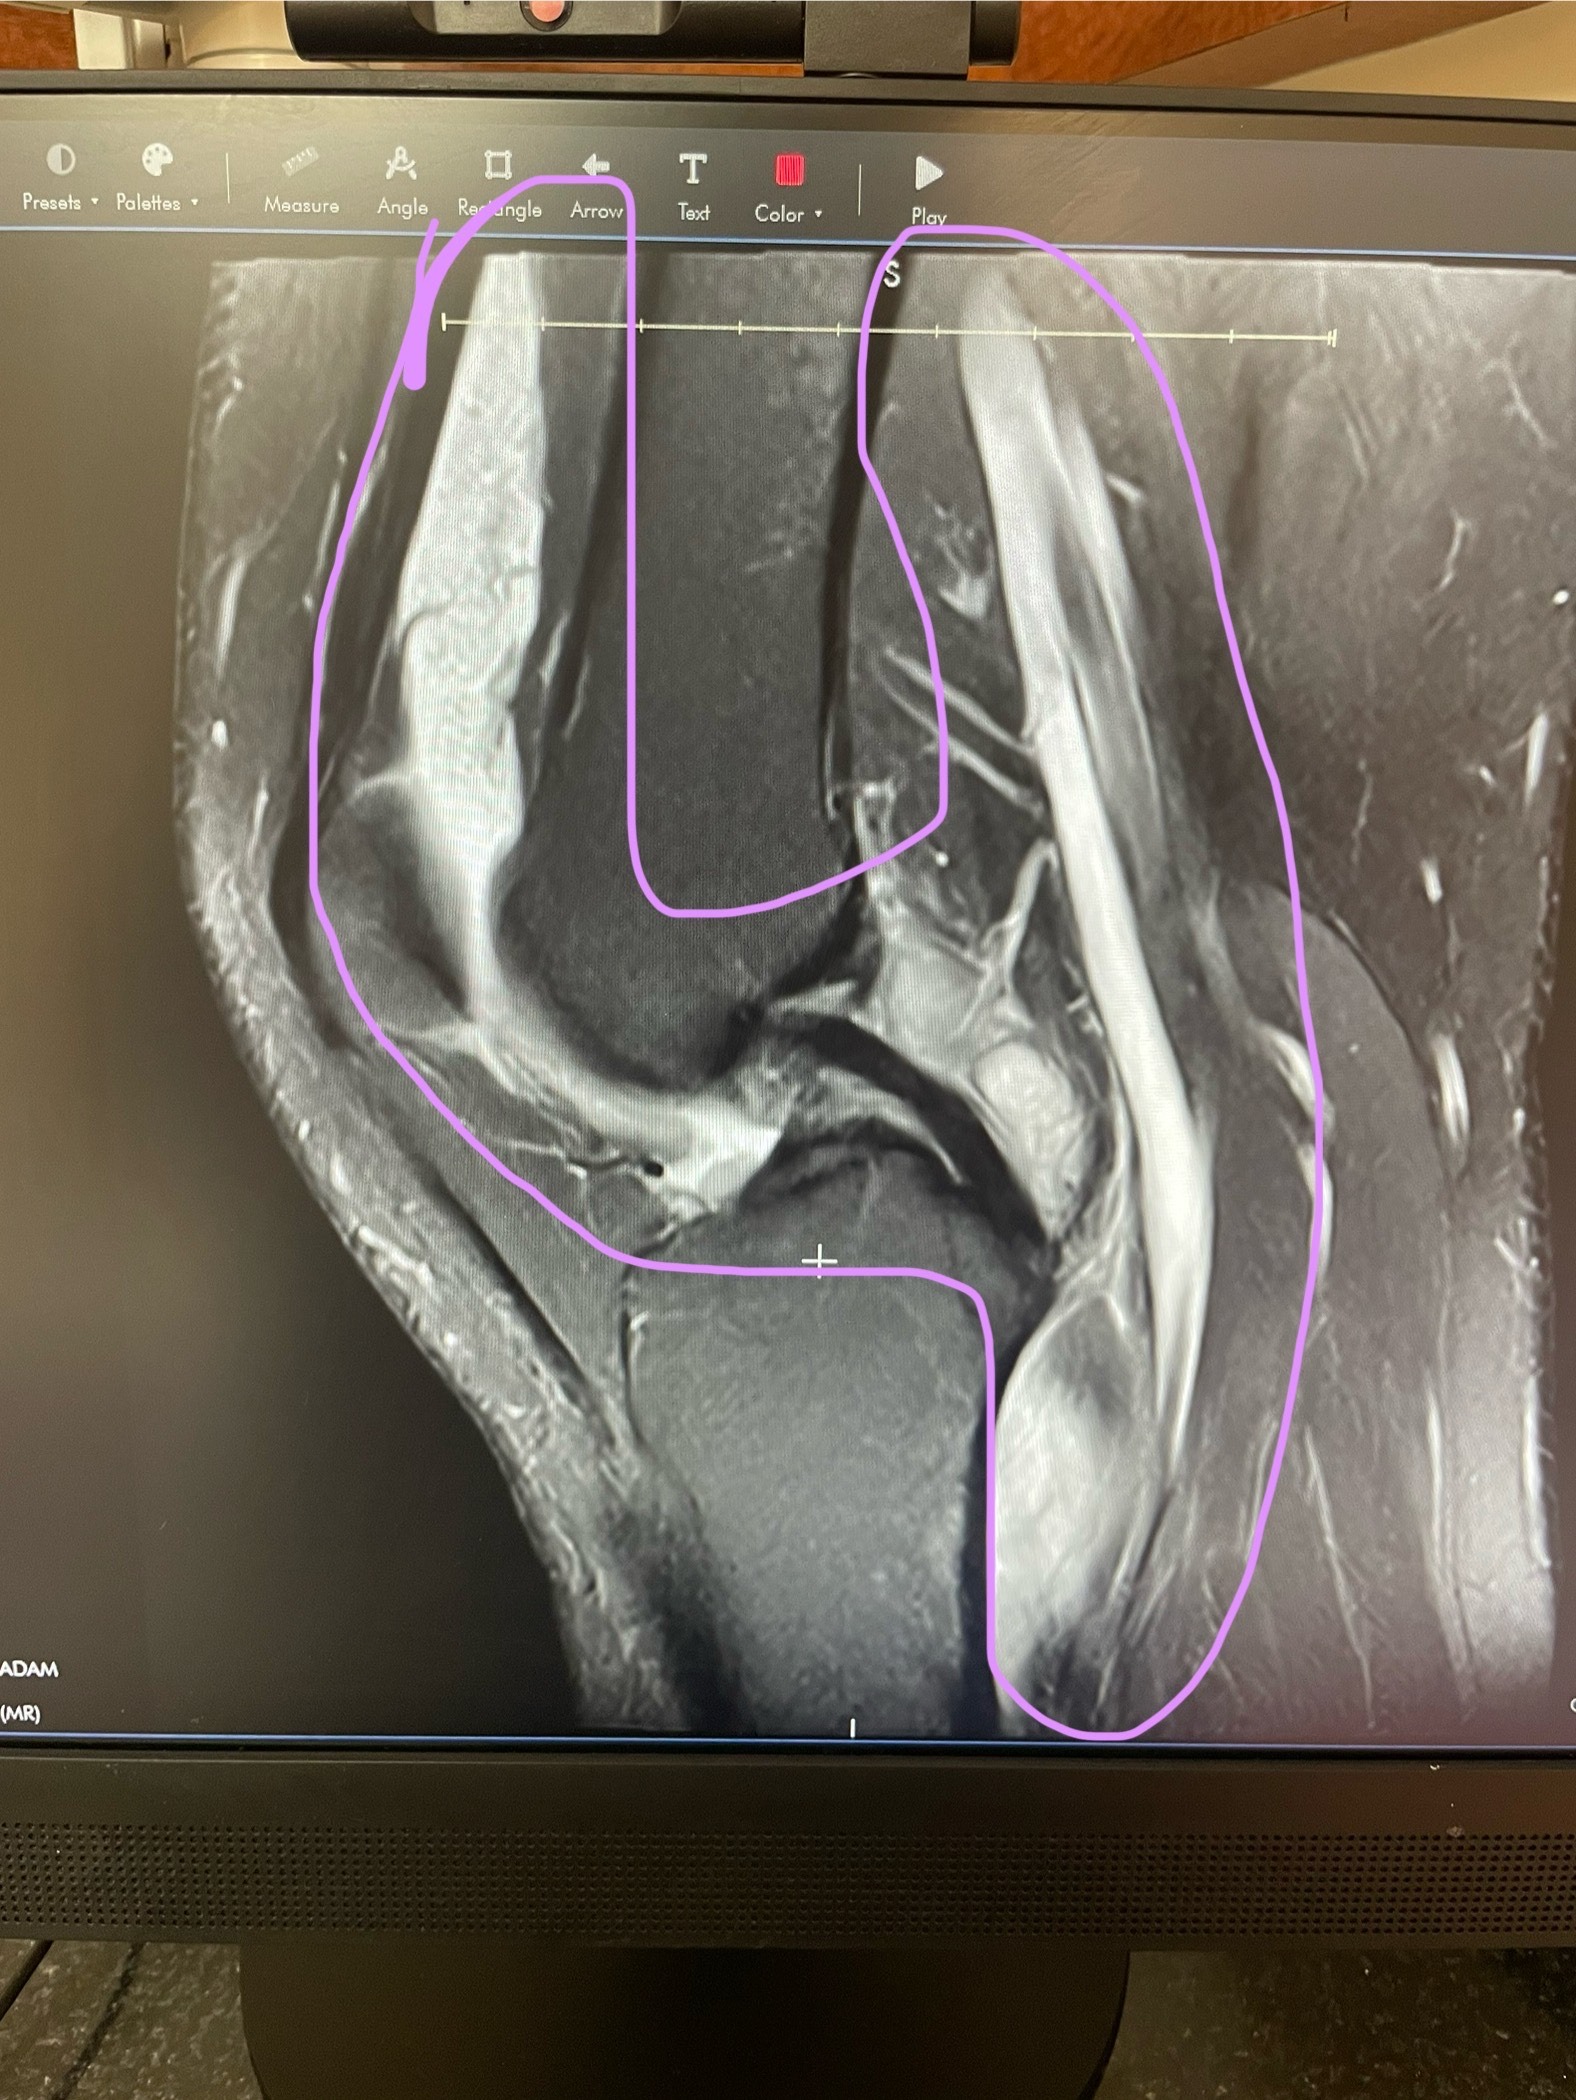

In February, Sasha injured their knee and we assumed it was a potential ACL tear. After months of medical neglect from a local primary practice, Sasha’s knee was left untreated. The pain, swelling, and mobility quickly worsened. Finally, we got an appointment with a sports medicine doctor and he issued an MRI immediately, something we had been fighting for for months. This is when we received a diagnosis.

In August of 2025, Sasha was diagnosed with Diffuse Tenosynovial Giant Cell Tumor (TGCT) - a rare degenerative joint disease. The doctors on Sasha's case confirmed statistics that around 43 in every million people are diagnosed a year and that they see only 1 - 2 cases a year. TGCT info below.

In easier terms, Sasha has a benign tumor that has taken over their entire knee joint, and has wrapped itself completely around it. Additionally, most of the cartilage in their knee is gone, meaning their bones are grinding together which add to the loss of mobility and pain. Their doctor also thinks that there is a meniscal tear due to the location and large nature of the tumor.